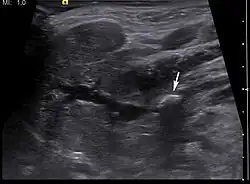

Diagnosis is usually made by characteristic history and physical examination. Diagnosis can be confirmed by x-ray (80% of salivary gland calculi are visible on x-ray), by sialogram, or by ultrasound.

- ^ "UOTW #70 - Ultrasound of the Week". Ultrasound of the Week. 24 April 2016. Retrieved 27 May 2017.